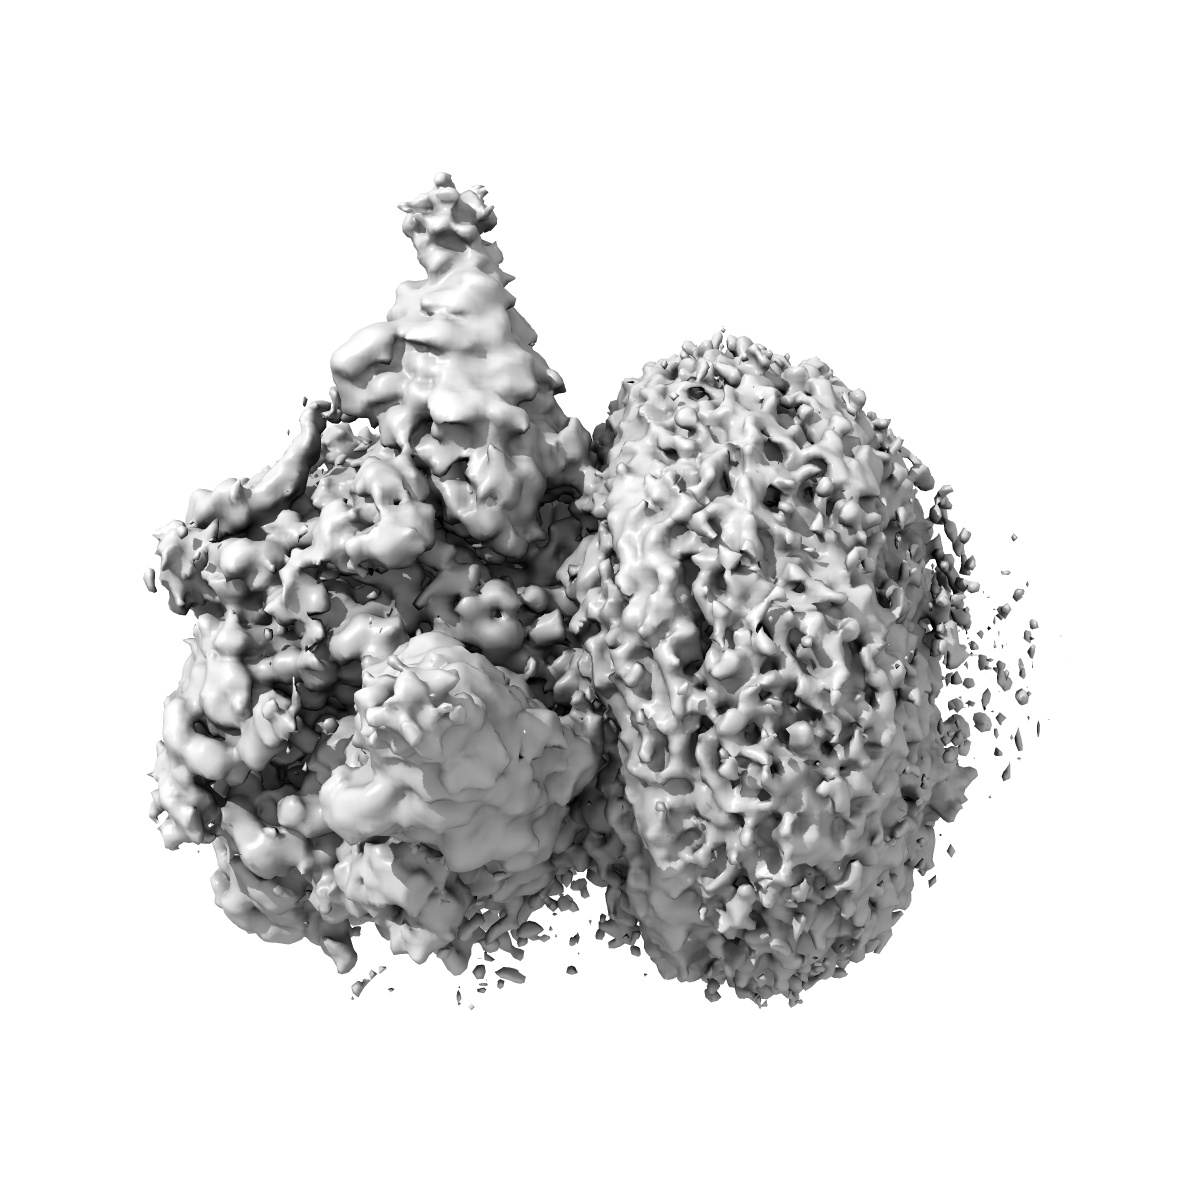

Cryo-EM structure of human full-length extrasynaptic alpha4beta3delta GABA(A)R in complex with GABA, histamine and nanobody Nb25 in a pre-open/closed state

Single-particle2.9 Å

Sample: Human full-length extrasynaptic alpha4beta3delta GABA(A)R in complex with histamine and nanobody Nb25